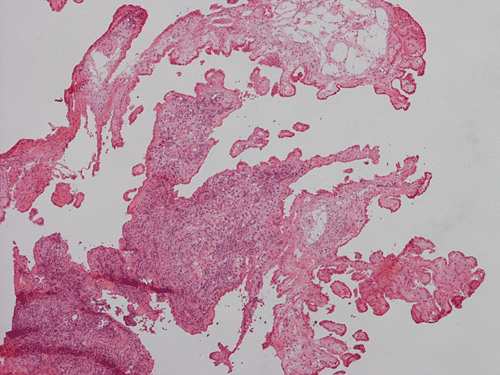

Pathology of the Case: The sample submitted for frozen section has a papillary structure which can be identified as the choroid plexus (Panel C). The center of the choroid plexus is expanded by some large cells accompanied by some smaller cells presumably lymphocytes (Panel D and E). On hematoxylin and eosin stain of the permanent sections, the tumor is composed of clusters of large cells in a background of lymphocytes. On higher magnification, the large cells have enlarged nuclei with prominent nucleoli. No trophoblasts or nor seminomatous component are identified. Immunohistochemistry demonstrated strong positive reactivity for placental alkaline phosphatase (PLAP) (Panel I) and CD117 (c-kit) in the large atypical cells (Panel J). The lymphocytes in the background are strongly immunoreactive for leukocyte common antigen (LCA) (Panel K) but negative for PLAP and CD117.

The discussion here will be limited predominantly to germinoma. Histologically, germinoma has very characteristic features heralded by large, atypical germinoma cells in a background of benign lymphocytes. The germinoma cells are usually huge, with a moderated amount of cytoplasm, and with prominent nucleoli. These cells, even though large, are rarely bizarre. The proportion of germinoma cells with lymphocytes can be highly variable. While most cases show a good mix of both component, the small biopsies yielded by endoscopic biopsy can sample in areas that are lymphocyte predominant or germinoma cell predominant areas which lead to diagnostic pitfalls. It should also be reminded that germinoma has a strong tendency to undergo granulomatous changes. Such granulomatous changes may completely efface the usually big cell-small lymphocyte classic pattern. These biopsies, however, would histologically suggest infection but the clinical history usually would not. Knowing the clinical history is often helpful. Trophoblastic cells could be seen and their presence may indicate a worse prognosis for germinomas. Non-seminomatous component such as embryonal cell carcinoma, yolk sac tumor (endodermal sinus tumor), and choriocarcinoma should also be identified if present.